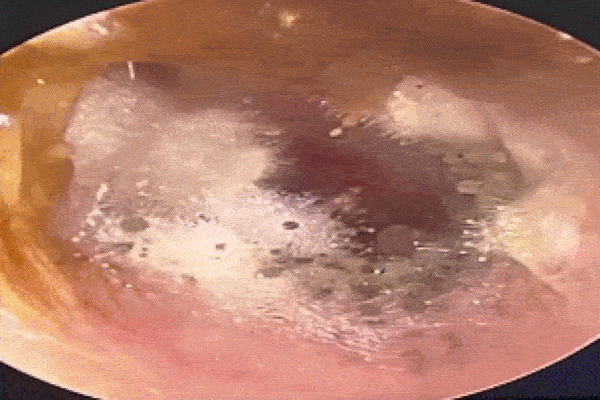

Tại Bệnh viện Nhân dân Thâm Quyến, Phó Giám đốc Khoa Tai mũi họng, bác sĩ Lyu Yanlu, tiết lộ một phát hiện gây sốc. Ống thính giác bên ngoài của bệnh nhân gần như bị lấp đầy hoàn toàn bởi cơ thể của một con gián, có chiều dài là 2,5 cm.

Theo các nhân viên y tế, đây là một con gián cái. Do trong trạng thái sống nên có nguy cơ đôi chân sắc nhọn của nó khiến ống tai của Lưu bị tổn thương thêm. Do đó, bác sĩ quyết định gây mê con gián để lấy nó ra một cách an toàn.

Lyu nhận thấy con gián có hình dạng khác thường, nó có một cái vỏ trứng màu vàng, sưng tấy, nổi rõ, cho thấy nó đang mang thai. Bác sĩ suy đoán rằng con gián có thể đang tìm nơi trú ẩn an toàn cho con của nó.

Sau khi gây mê cho con côn trùng, đội ngũ y tế đã tỉ mỉ loại bỏ vỏ trứng và sau đó là con gián dưới sự hướng dẫn nội soi. Việc loại bỏ là rất quan trọng vì bất kỳ quả trứng nào còn sót lại đều có thể nở trong ống tai.